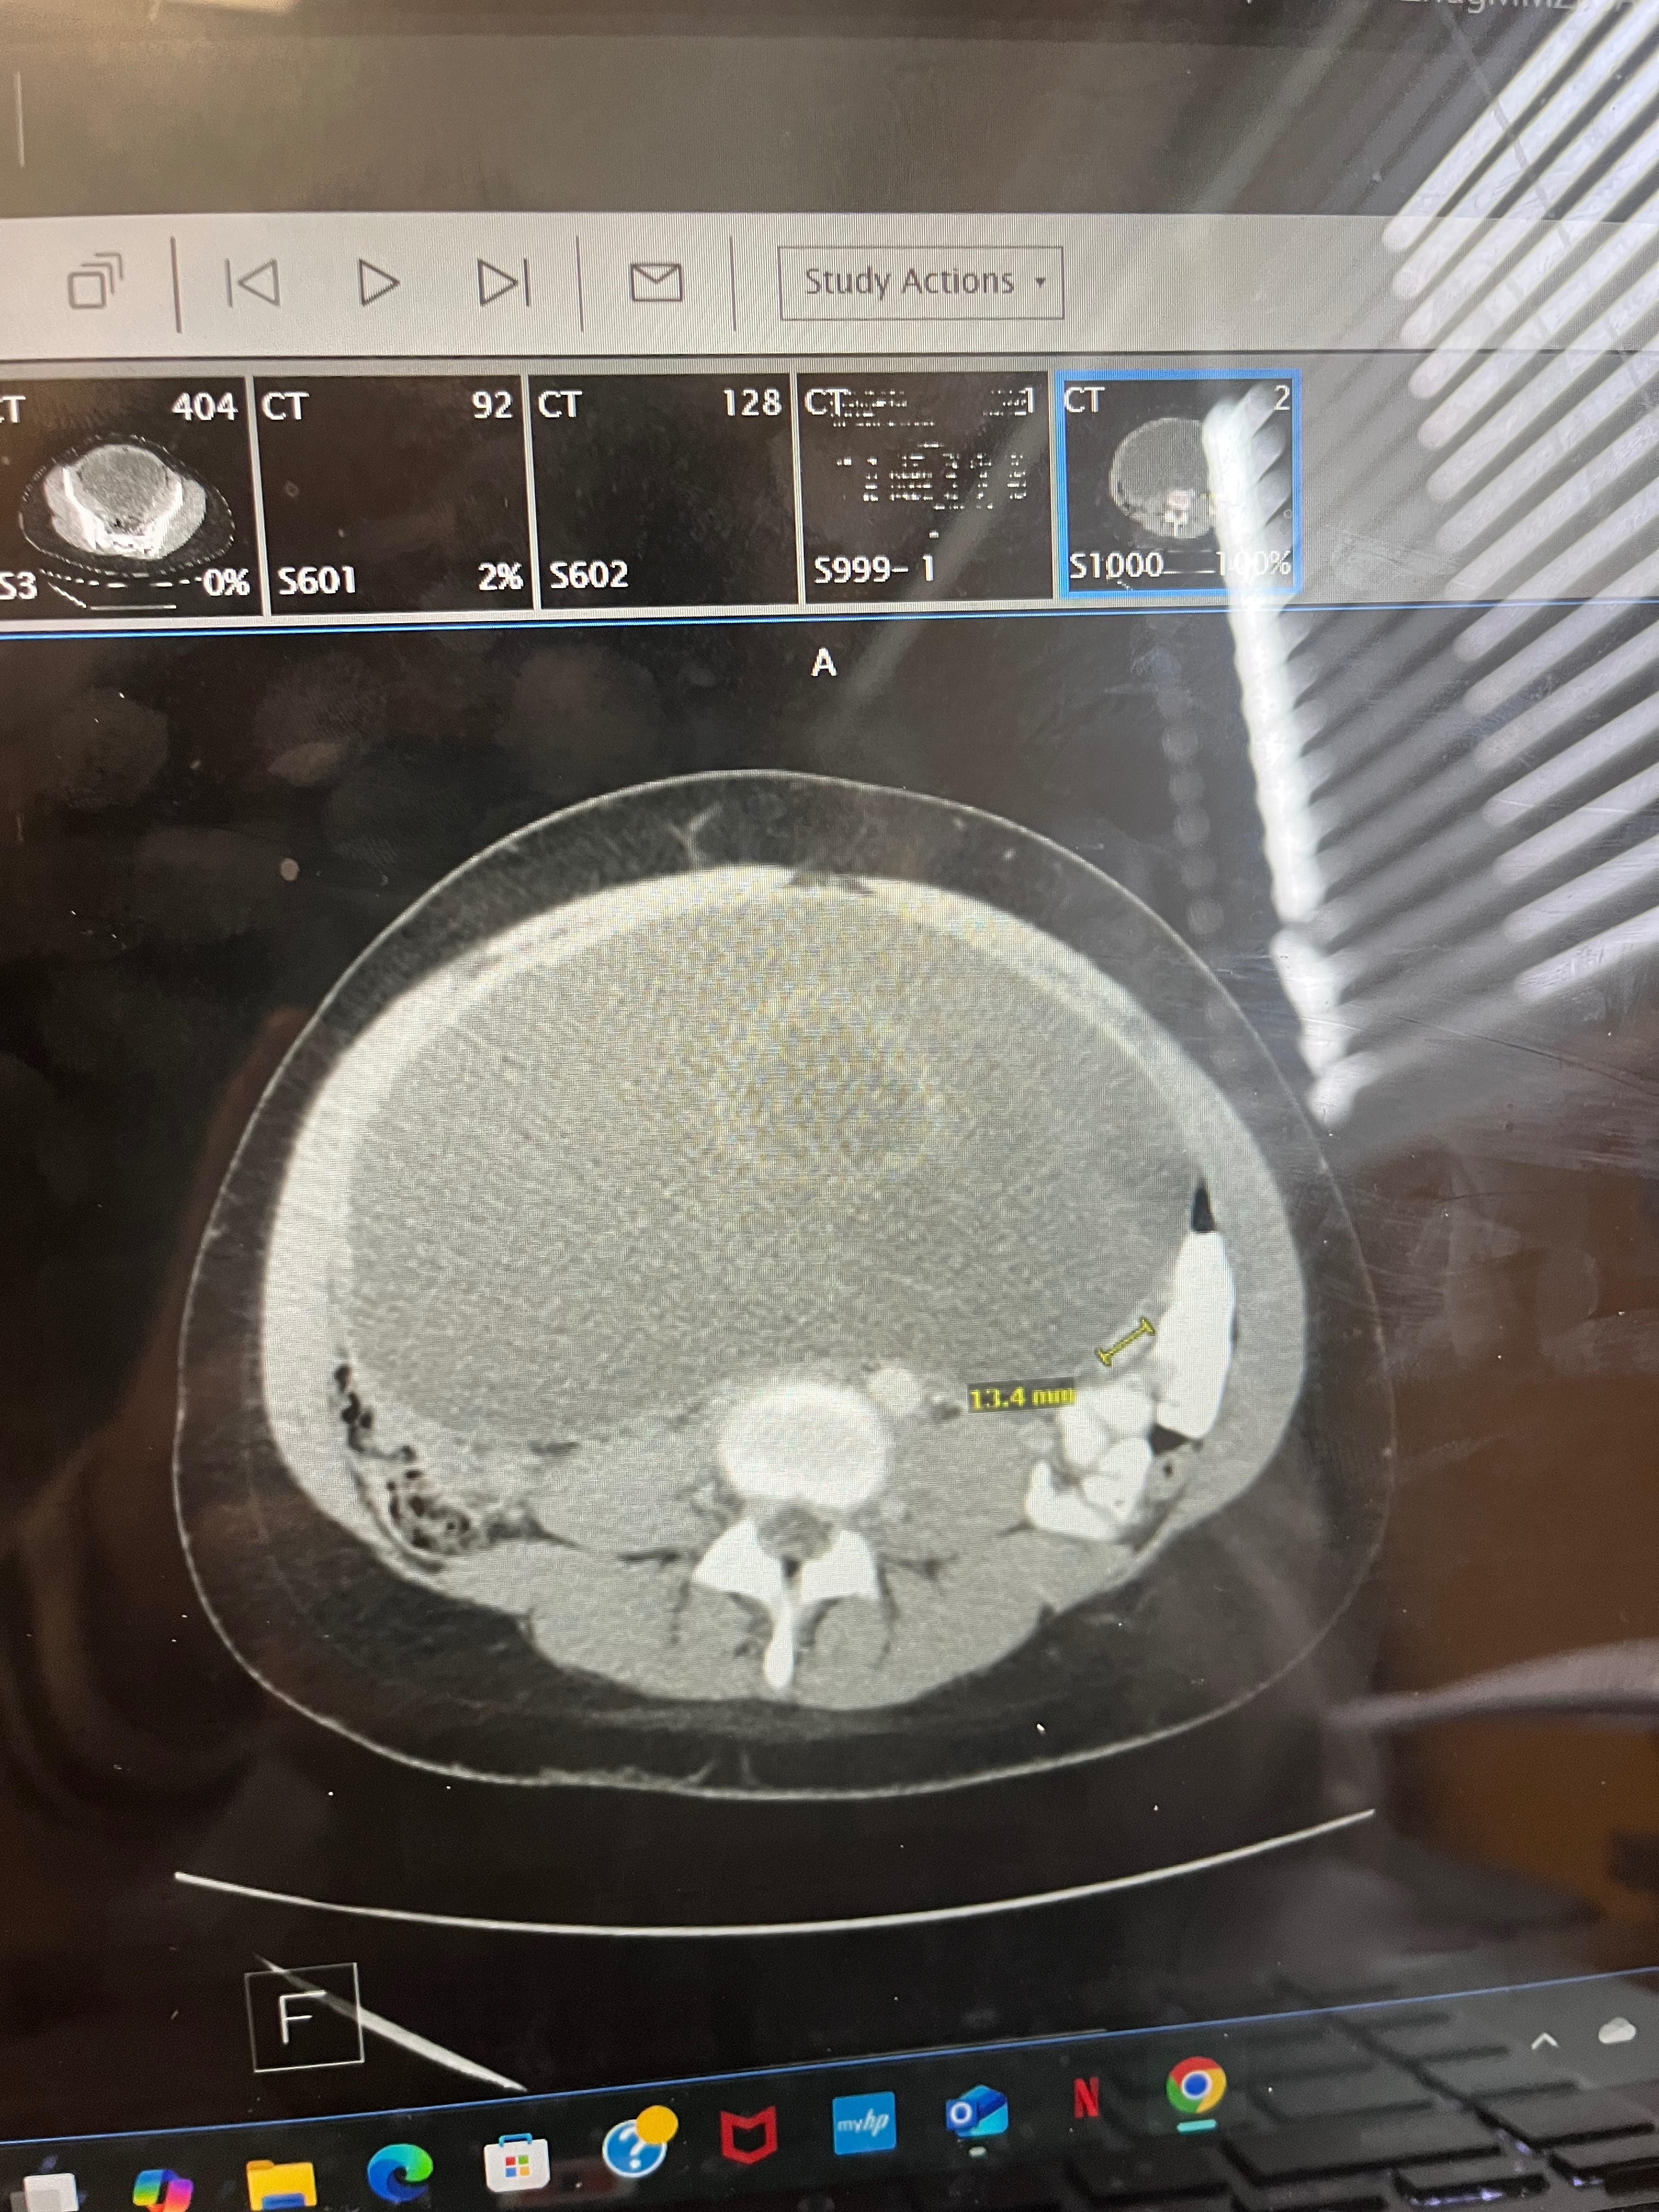

Hi, my name is Mira and I’m currently pursuing a physics degree at the University of Illinois Urbana-Champaign. My freshman year, I was diagnosed with mucinous ovarian cancer, which caused me to travel back home to receive surgery and further treatments. Through surgery, I lost my ovary, which puts me at higher risk of becoming infertile, and I’m currently seeking to receive fertility treatment.